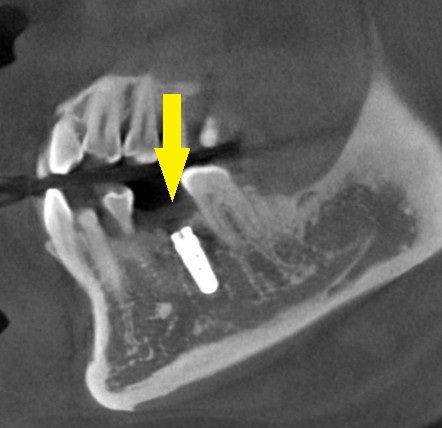

CTを撮影してみると、確かに、骨幅が狭く、十分な骨の厚みを確保してインプラントを長期に安定した状態にしたいとなると、骨を増やす手術が必要でした。

人工骨を使用しての骨造成術を併用して、インプラント埋入を行なうことで了承されましたので、本日、同手術を施行しました。

下の写真に手術前後のCTを示します。